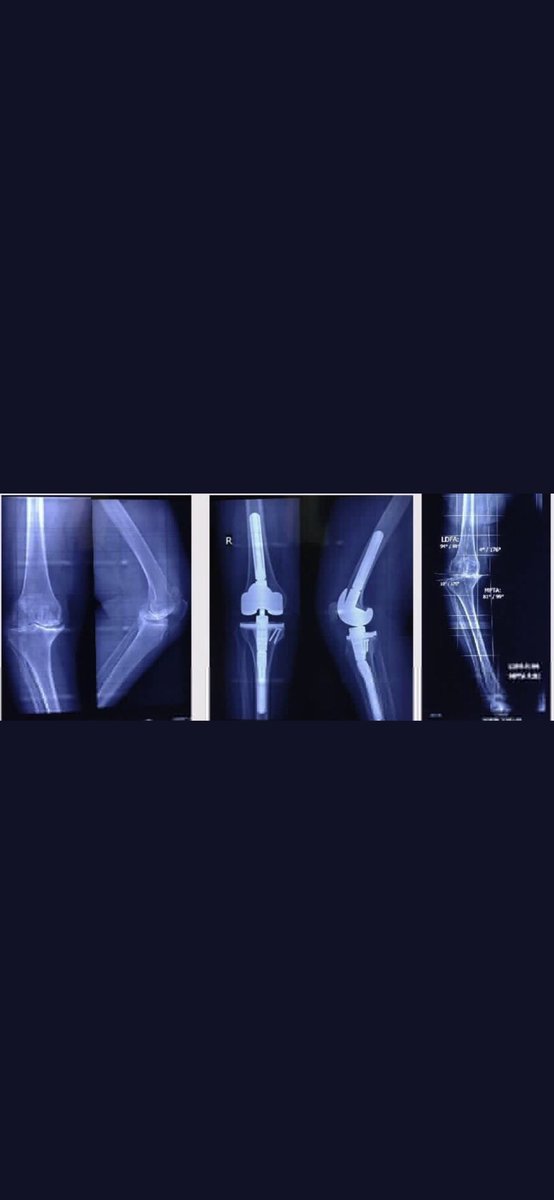

- يمكن اجراء عملية المفصل الصناعي بدون قطع في وتر العضلة الرباعية للفخذ .

لكشف مفصل الركبة وإعطاء مجال رؤية أفضل يحتاج جراح العظام لعمل قطع في وتر العضلة الرباعية للفخذ مما يسهل عليه العملية الجراحية . مايشاع عن وجود عمليات حديثه بدون قطع في وتر العضلات هي دعايات مضللة .

- لايمكن للمريض المشي بعد العملية مباشرة وقد يحتاج وقتا اطول حتى يتمكن من ذلك .

يمكن للمريض المشي مباشرة بعد العملية ويساعده في ذلك قدرة الطبيب المعالج او المخدر على التحكم في الالم مابعد العملية وقد شهدت الفترة الاخيرة تطورا ملحوظا بهذا الصدد سواء بالادوية او الحقن الموضعي .

- لايوجد فرق بين اجراء عملية المفصل الصناعي في حين الوصول للمراحل المتقدمة أو عملها مبكرا .

تأخير عملية استبدال المفصل الصناعي يجعل منها اكثر تعقيدا وقد يؤثر على جودة الاربطة الجانبية وكذا ثبات المفصل مايتطلب الحاجة لمفصل صناعي من نوع خاص قد يقل معه العمر الافتراضي له .